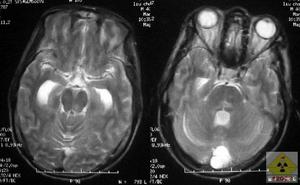

早期下肢發緊,行走不穩,晚期一側下肢或四肢癱瘓,二便失禁或尿瀦留,受壓脊髓節段以下感覺障礙,肌張力增高,反射亢進,椎體束征陽性,X線片示:椎間隙狹窄,椎體後緣增生較嚴重並突入椎管。CT,MRI檢查示:椎管變窄,椎體後緣增生物或椎間盤膨出壓迫脊髓。